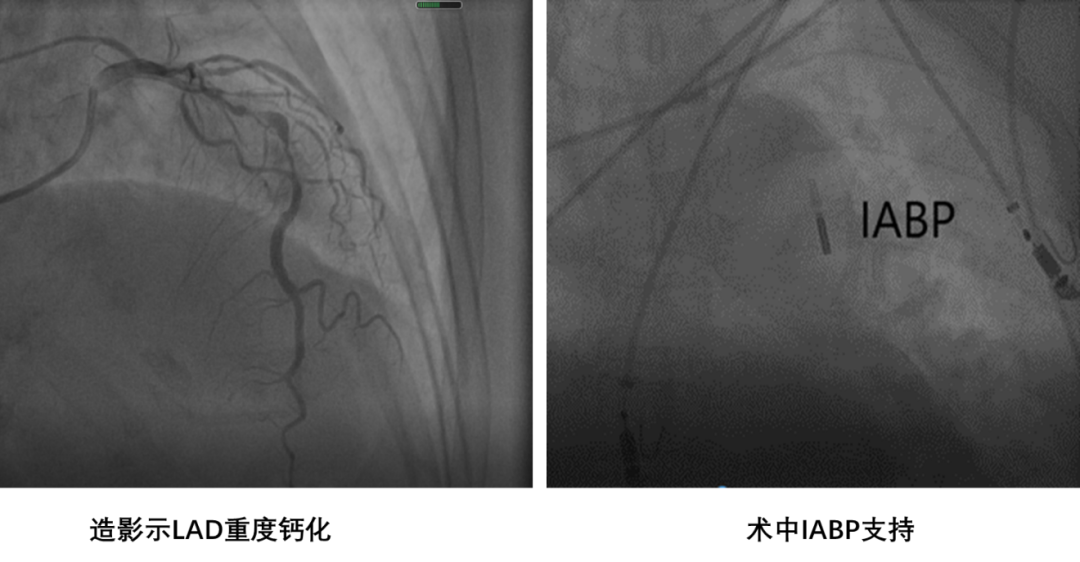

患者为85岁老年女性,以突发胸痛9小时入院。入院诊断为急性非ST段抬高型心肌梗死。入院后反复出现心绞痛发作,行急诊冠脉造影提示三支病变,前降支重度钙化,建议患者行冠脉搭桥手术治疗,患者及其家属表示拒绝。丛洪良教授在充分分析患者病情和冠脉病变特点后,决定在IABP的支持下行Shockwave冲击波球囊行碎石手术。

由于前降支病变钙化极其严重,多次使用球囊扩张后,IVUS导管仍不能通过病变,无法进行术前评估,Shockwave球囊也无法通过病变,决定先行旋磨治疗。

经1.5mm旋磨头旋磨8次后,旋磨头不能完全通过病变,而且患者出现顽固性无复流,经微导管多次给与腺苷、硝普纳以及欣维宁后前降支血流有所改善,但效果不明显,前壁导联心电图ST段抬高。随后使用2.5mm球囊到达病变后,多次加压扩张难以使钙化狭窄的部位充分扩张,立即使用Shockwave冲击波球囊行碎石手术。经过8个周期(80个脉冲)冲击波治疗后,IVUS证实钙化病变出现断裂,最终成功植入支架,达到理想的支架膨胀贴壁效果。